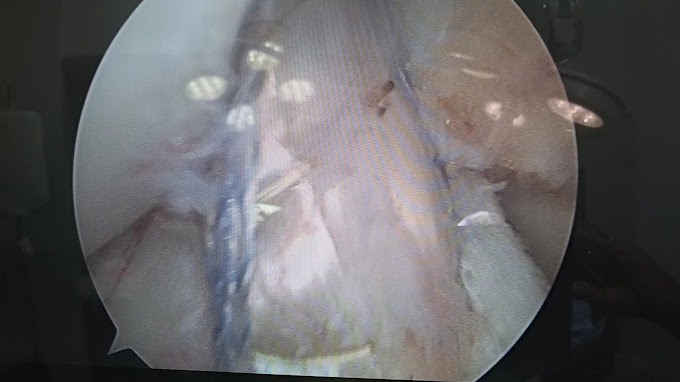

Arthroscopy

Minimally invasive joint surgery for accurate diagnosis and treatment of joint issues.